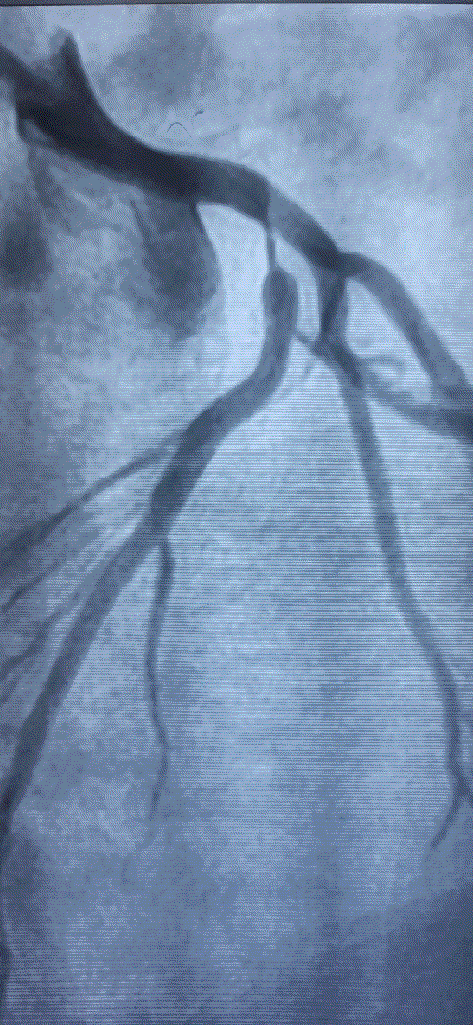

How do you explain this ? 99% occlusion still TIMI 3 flow ?

Answer

A. It could be a parallax error. Lesion may not be tight. Should be seen in other views.

B . Forcible Injection by the operator, make it an artificial TIMI -3 flow.

C .Such flows are very much possible .It Indicates a healthy distal micro-circulation a vascular bed in a fully dilated mode.

D. TIMI flow is not reliable here . We need TIMI frame count to confirm.

Follow up questions

1.How much will be the FFR ?

Likely to be less than . 8 definitely , but surprises can happpen

2.Can he be asymptomatic ?

Unlikely.

Final message

Coronary occlusions are ominpresent . While we have mastered the art of successfully taming these anatomical enemies , we are still very much ignorant what these lesions actually do, to the physiology, inspite of half a dozen flow reserve Indices we have.(FFR,iFR, rFR,qFR, dP/dT ,etc)

The question is, at what level of obstruction, it really limits the coronary bllod flow significantly ( both at rest and exertion) . One thing is clear , it is higly variable & Individualistic, the secrets of which lies deep, in the domain of invisible micro-vascular network integrity.